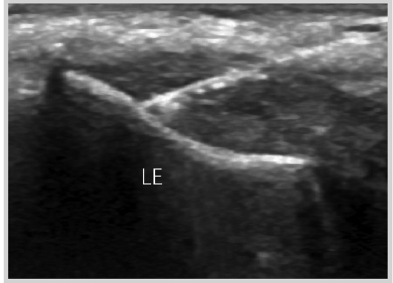

테니스 엘보우는

초음파 검사상

힘줄이 어두워지고,

지저분해지고

퉁퉁 부어 두꺼워집니다.

팔꿈치 외측 힘줄이 어두워지고, 지저분해지고, 부어있습니다.

초음파 유도 전기침 치료

힘줄에 정확하게 들어가는 "침(Needle)"이 보입니다.